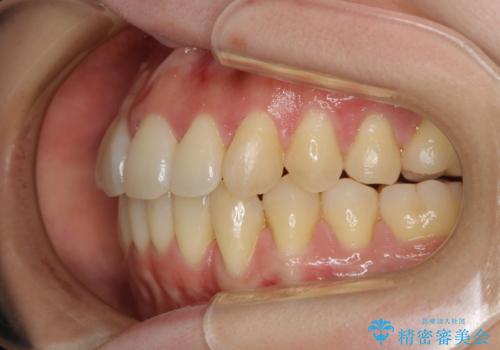

本来は外科ケース:インビザラインで前歯の重度がたつきとオープンバイトの改善

- 前歯のがたつきが気になるとご相談にいらした患者様です。矯正検査の結果、骨格的なズレが大きかったため当初の治療計画では外科矯正をご案内しました。ご本人が手術を望んでおらず、可能な限りの改善を目指すことを目標に治療を開始しました。

元々の骨格的なズレが大きかったため、当初は外科矯正をご提案していました。患者様の強いご希望により、非外科的な処置のみで可及的な改善を目指すことを目標に治療を行いました。以前よりもしっかり噛めるようになり、見た目も劇的に改善したことで大変ご満足いただけました。